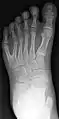

У людей и животных она может проявляться как на одной, так и на обеих руках. Обычно дополнительный палец представляет собой небольшой кусочек мягкой ткани, которую можно удалить. Иногда это просто кость без суставов; очень редко лишний палец бывает полноценным. Дополнительный палец чаще всего образуется со стороны мизинца, реже на стороне большого пальца и очень редко между средними пальцами. Обычно лишний палец является аномальным разветвлением обычного пальца, редко возникает на запястье, как обычный палец.

![]() |

![]() | |

postaxial |

preaxial |